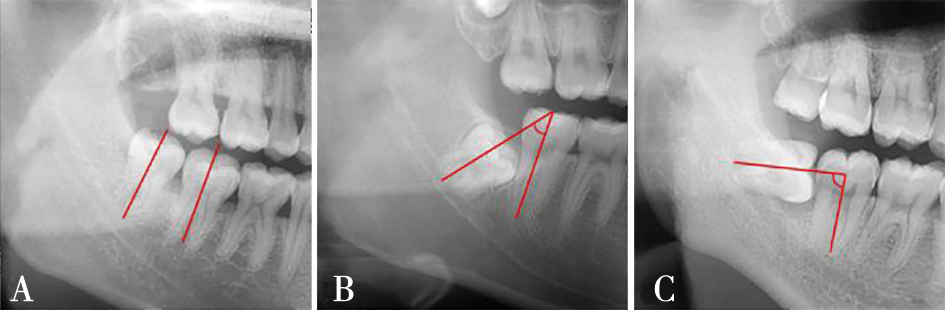

| Winter分类(曲面断层片) | 近中 | 484 | (50.26%) | 479 | (49.74%) | <0.000 1* | |

| 水平 | 566 | (52.85%) | 505 | (47.15%) | |||

| 垂直 | 1 046 | (77.20%) | 309 | (22.80%) | |||

| Pell-Gregory分类(基于第二磨牙咬合平面,曲面断层片) | 高位 | 1 115 | (81.15%) | 259 | (18.85%) | <0.000 1* | |

| 中位 | 786 | (51.37%) | 744 | (48.63%) | |||

| 低位 | 195 | (40.21%) | 290 | (59.79%) | |||

| Pell-Gregory分类(基于下颌升支,曲面断层片) | Ⅰ类 | 762 | (84.57%) | 139 | (15.43%) | <0.000 1* | |

| Ⅱ类 | 888 | (63.66%) | 507 | (36.34%) | |||

| Ⅲ类 | 446 | (40.81%) | 647 | (59.19%) | |||